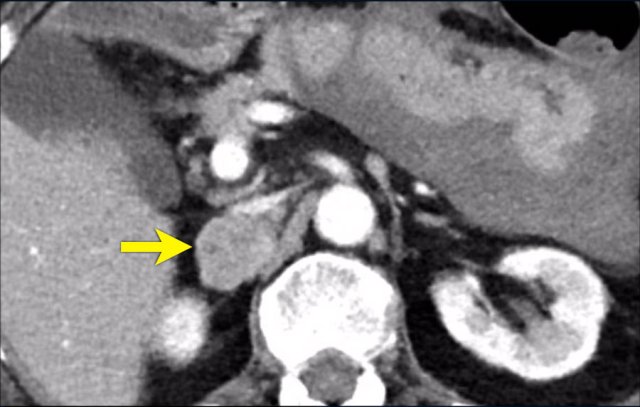

Metastasis of an adenocarcinoma Metastasis of an adenocarcinoma

The image shows a heterogeneous ill-defined mass larger than 4 cm.

There is a hypo-enhancing center, which is probably the result of central necrosis.

In this particular case a biopsy was performed and revealed an adenocarcinoma, probably from primary lung carcinoma.

Surprisingly, extensive imaging analysis, including FDG PET-CT, did not detect a primary tumor, however.

Adrenocortical carcinoma Adrenocortical carcinoma

The image shows a 67 mm heterogeneously enhancing relatively well defined lesion.

This proved to be an adrenocortical carcinoma, after resection.